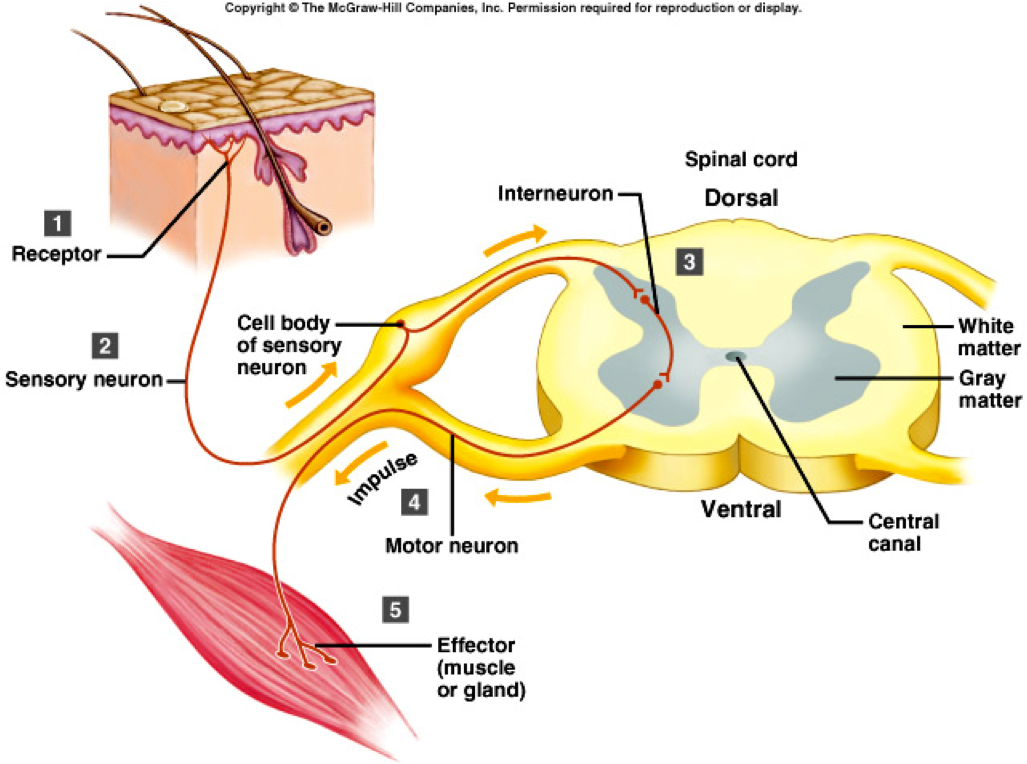

4. Steps involved with a reflex arc

a. Receptor picks up sensory impulse

b. Sensory impulse travels along spinal nerve, past dorsal root ganglion, through the dorsal root and enters the dorsal gray horn (same side of the body).

c. Sensory impulse is transferred to the ventral gray horn

1. Monosynaptic - directly from sensory to motor neuron-- most rapid

2. Polysynaptic - from sensory to interneuron to motor neuron--slower and more complicated response

d. Ventral gray horn sends motor impulses out of spinal cord, through the ventral root and along spinal nerves to muscles that will respond to the sensory stimulus

e. Effector responds.